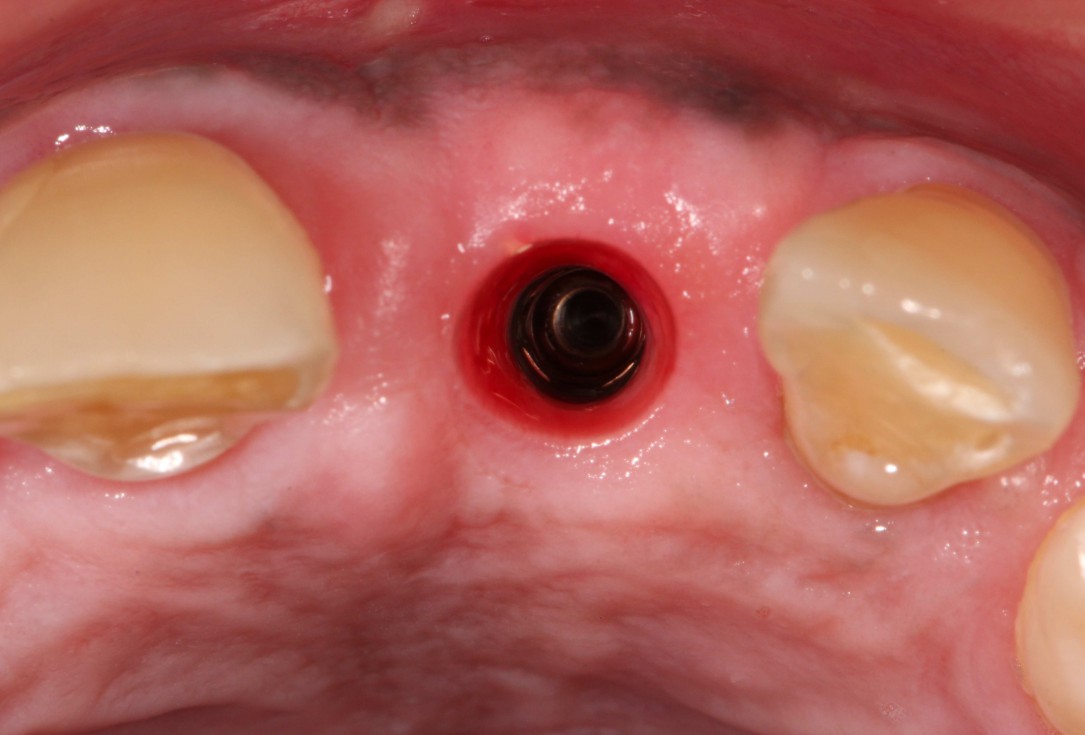

15/19 - Clinical situation after removal of the healing abutment

GBR with cerabone® and Jason® membrane in the front tooth region - Dr. H. Maghaireh